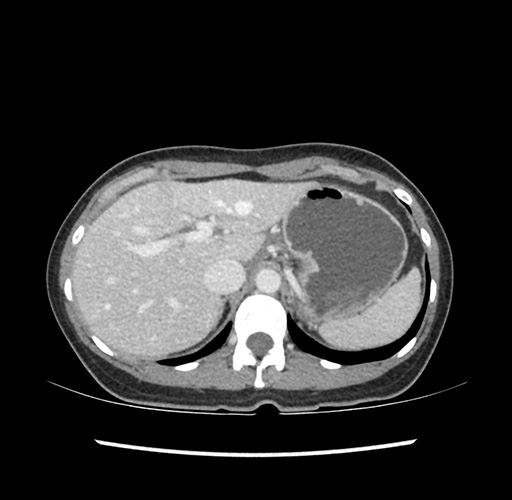

Imaging Analysis

Look through the patient's CT scan to identify any areas of concern for the necessary procedure.

Based on your CT findings, which issue(s) would give reason for "planned slowing down moment(s)" in this case?

Considering a standard left lateral sectionectomy procedure, what step(s) of the operation would you do differently in this case ?